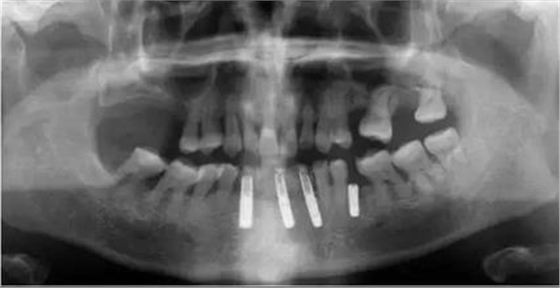

手術(shù)導(dǎo)板數(shù)據(jù)發(fā)送至成都登特,通過BEGO打印機(jī)打印出導(dǎo)板,切削出臨時(shí)冠

臨時(shí)冠就位,即刻修復(fù),無咬合接觸

修復(fù)后全景片

1:本病例的難度在于高骨密度

的條件下如何順利植入植體

2:數(shù)字化修復(fù)時(shí),

種植臨時(shí)修復(fù)體可能難以就位,

特別是多顆牙的修復(fù)